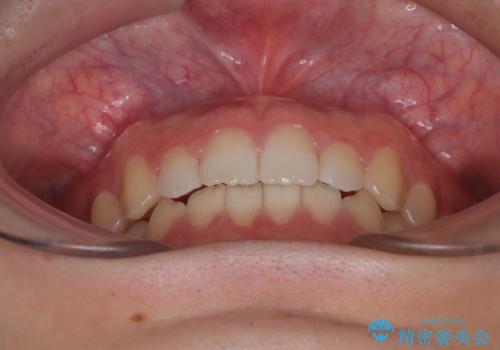

患者様は「できるだけ目立たない矯正治療」を希望されていたため、インビザラインを用いた治療計画を立案しました。

インビザラインは透明で装着していても気づかれにくく、日常生活やお仕事への影響を最小限に抑えながら治療を進めることが可能です。

そこで矯正治療と並行して**MFT(口腔筋機能療法)**を実施し、舌や口周囲筋の正しい使い方を習得していただきました。